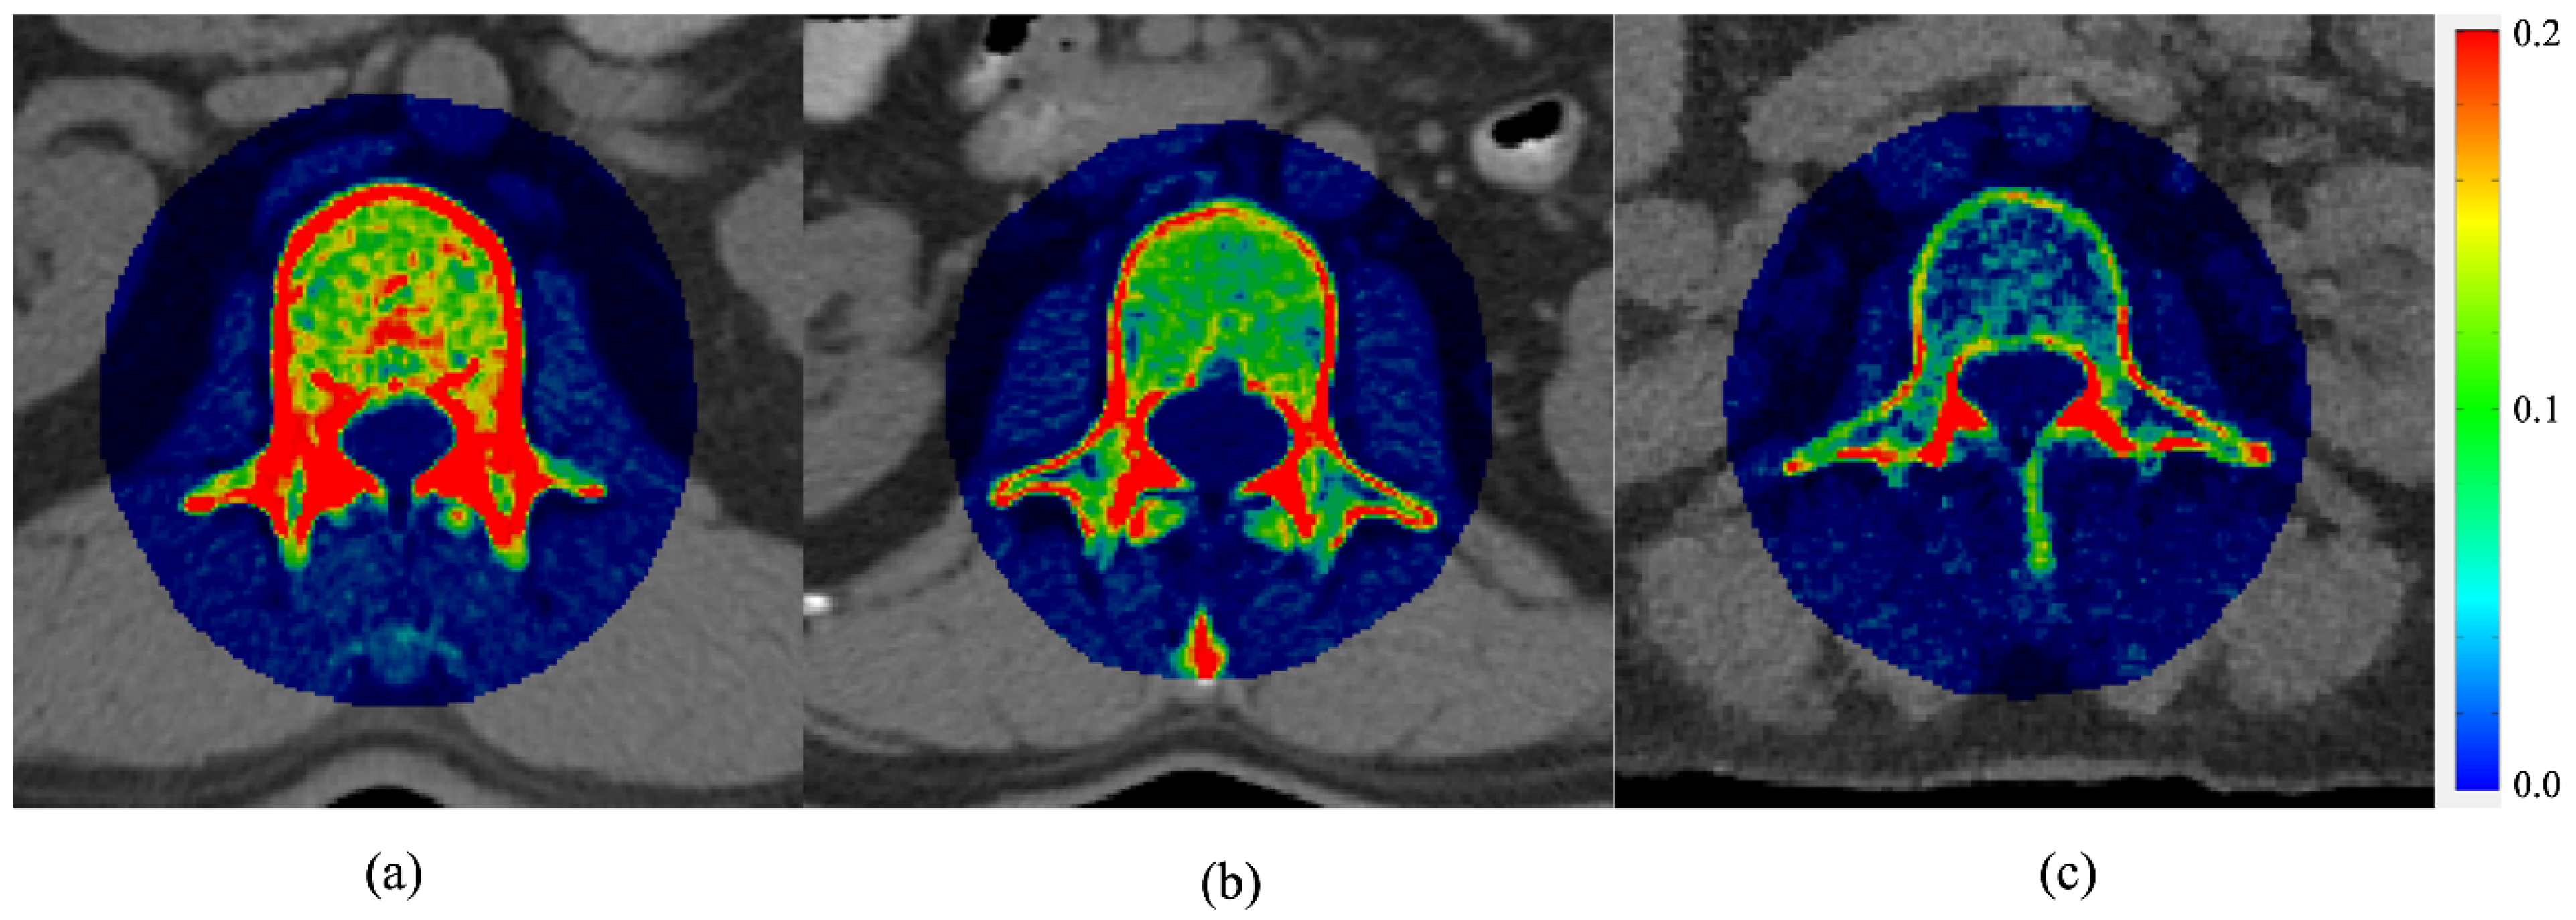

2.1. Two-Compartment Model

- Lin, H.; Peng, S.; Wu, J.; Shih, T.; Chuang, K.; Shih, C. A Novel Two-Compartment Model for Calculating Bone Volume Fractions and Bone Mineral Densities from Computed Tomography Images. IEEE Trans. Med. Imaging 2017, 36, 1094–1105. [Google Scholar] [CrossRef] [PubMed]